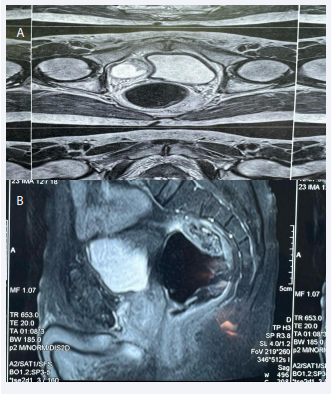

The patient underwent MRI, which revealed a 90x63x60 right latero-vesical partitioned cystic mass, initially suggestive of a cystic lymphagion (Figure1).

Figure 1: MRI images in the axial (A) and sagittal (B) showing the latero-vesical mass.